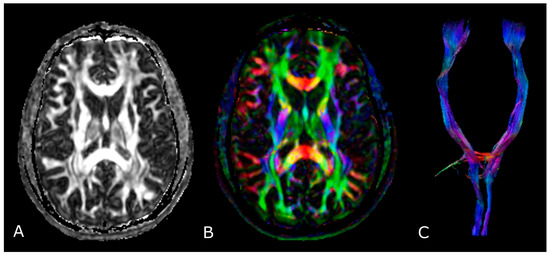

4.2. Diffusion Tensor Imaging: Technical Notes and Clinical Application

4.2.1. Tumor Grading and Extension

4.2.2. Presurgical/Intraoperative Assessment

4.2.3. Radiotherapy/Radiosurgery Planning